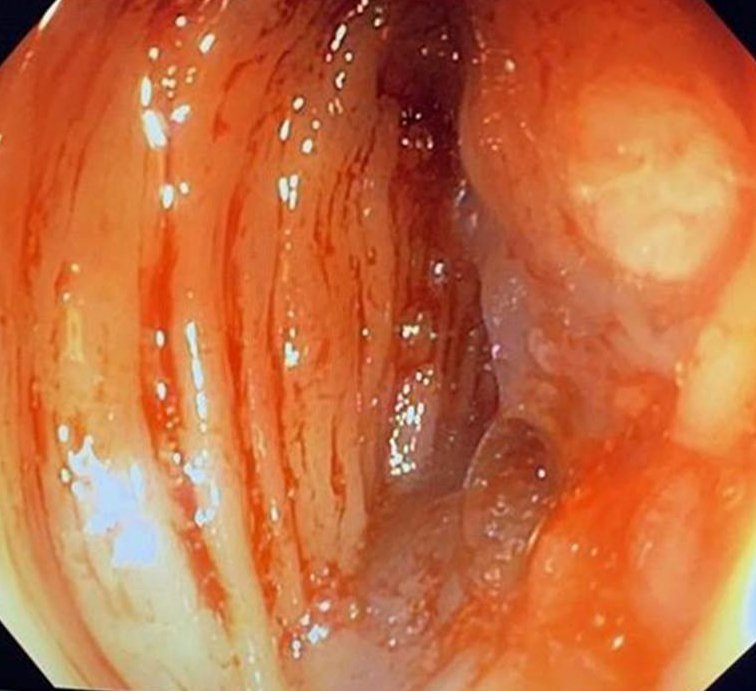

Una nueva TC de estadificación demostró la infiltración tumoral del músculo ilíaco y el nervio crural izquierdo. La arteria ilíaca externa se encontraba en íntimo contacto sin invasión aparente. Se objetivó una colección sobre la pared abdominal con relación a la cicatriz mediana (Fig. 2). No había evidencia de diseminación a distancia. Los marcadores tumorales CEA y CA 19-9 fueron normales.

Figura 2: Se observa el engrosamiento del colon descendente fistulizado hacia el músculo ilíaco izquierdo, con una colección en su interior (flecha sólida). b) Otra pequeña colección ubicada debajo de la línea media también se incluyó en la resección (flecha vacía).